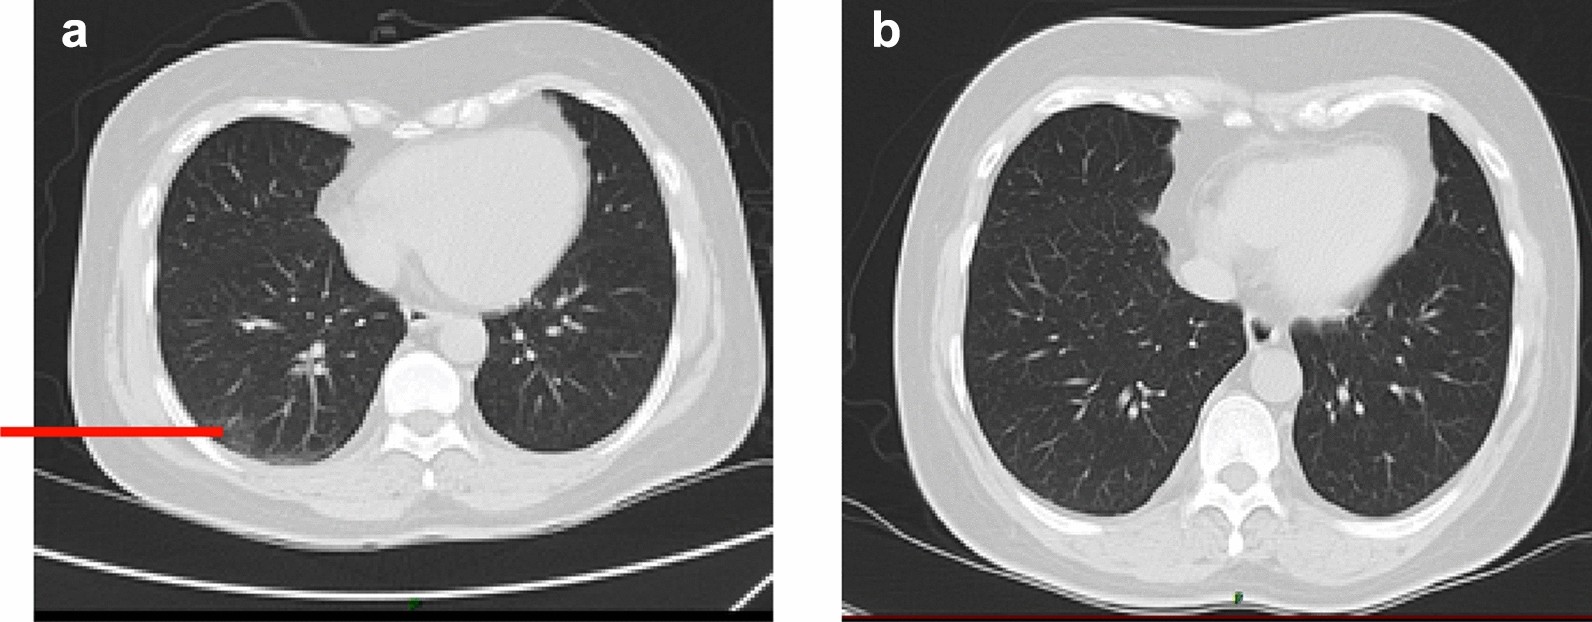

Fig. 3From: Case report: one case of coronavirus disease 2019 (COVID-19) in a patient co-infected by HIV with a normal CD4+ T cell countThe CT scan on Day 5(a) and Day 15(b)Back to article page